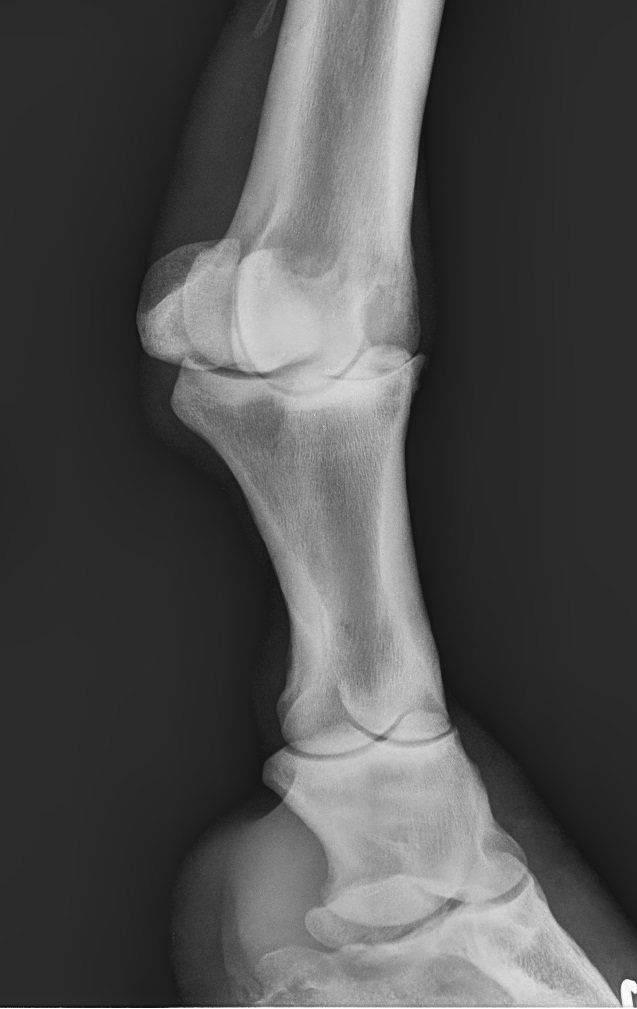

Bone Spavin disease (Bone Spavin), a form of osteoarthritis that affects the distal intertarsal and tarsometatarsal...

The prognosis of an anterior subluxation of the fetlock joint (metacarpal/proximal phalangeal joint) in jumping horses...

Most common causes that favor the appearance of Osteoarthritis in Pastern Joint in Jumping Horses.

Degenerative joint disease (DJD), often referred to as “osteoarthritis”, is a very common cause of lameness in...

Arthritis in horses is a disease that can affect them just as it does in humans by influencing their physical...